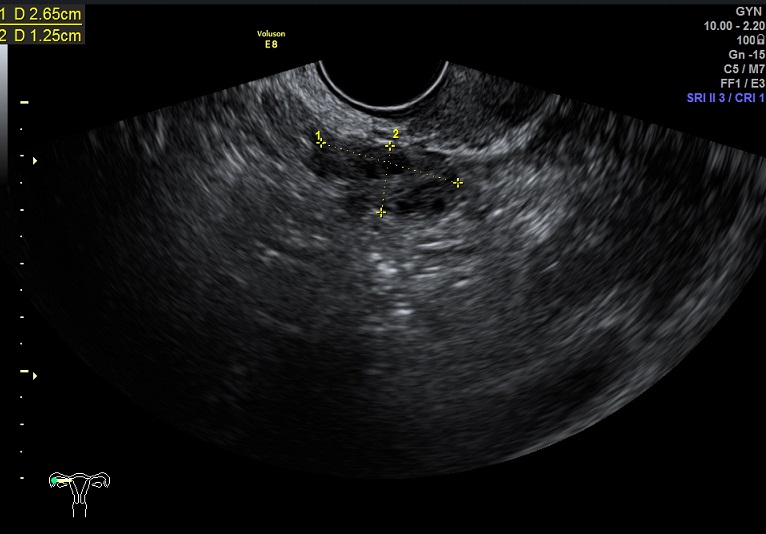

2015-1-12,月经第3天检查

左卵巢: 大小2.9x2.3x1.4cm 体积:4.8 窦卵泡:4个 卵巢间质血流:9.8cm/s RI:0.49

右卵巢: 大小 2.6x1.6x1.3cm 体积:2.8 窦卵泡:2个 卵巢间质血流:11.5cm/s RI:0.52